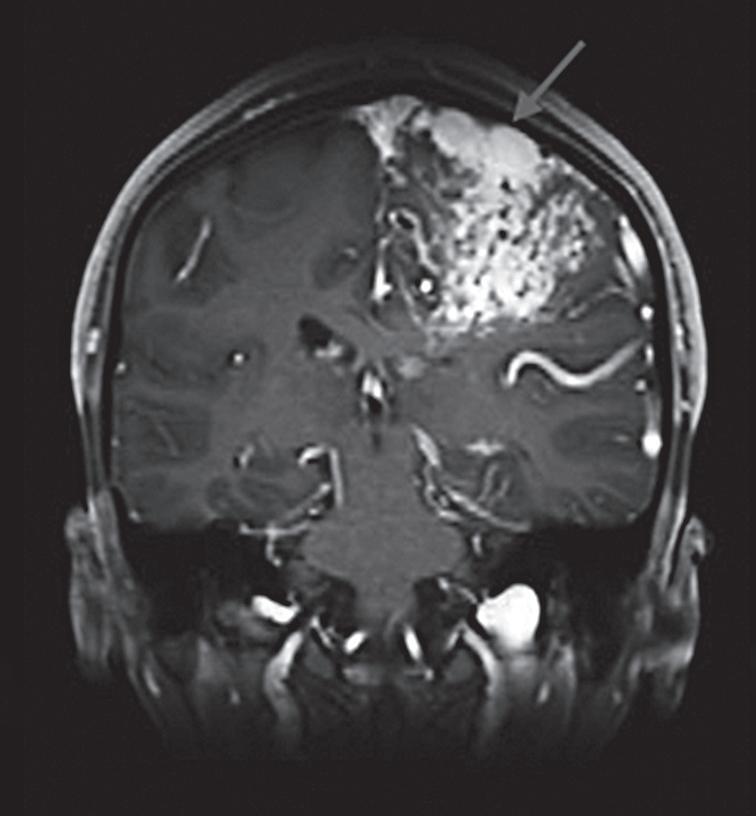

Fig. 1-8. (a-c) RNM T1 com contraste, cortes sagital (a), coronal (b) e axial (c) demonstrando MAV não rota com nidus localizado no lobo occipital à esquerda (setas longas). (d) Arteriografia digital cerebral com injeção de contraste via carótida direita (AP) mostrando a contribuição da carótida direita na irrigação da MAV contralateral. (e,f) Com injeção de contraste via carótida esquerda, em Perfil e AP respectivamente, observa-se nidus compacto nutrido por ramos da artéria cerebral média à esquerda e a veia de drenagem precoce se dirigindo para o seio sagital superior. Projeções em AP (g) e em perfil (h) demonstrando a contribuição do sistema vertebrobasilar por meio de ramos distais da artéria cerebral posterior à esquerda e drenagem para os seios sagital superior e sigmoide à esquerda (setas curtas).

Fig. 1-14. RNM encéfalo, T2 axial (a) e coronal (b), demonstrando MAV grau 2 no lobo parietal esquerdo.

Arteriografia cerebral (c) AP e (d) em perfil, demonstrando a irrigação pelos ramos da artéria cerebral média (ACM) e anterior (ACA), com drenagem pela veia de Labbé, no seio transverso sigmoide.